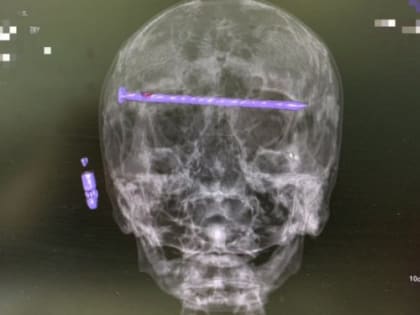

Уникальная операция в Нижнем Тагиле: врачи извлекли гвоздь длиной 15 см из головы пациента

78-летний мужчина получил травму, которая потребовала экстренного вмешательства нейрохирургов.